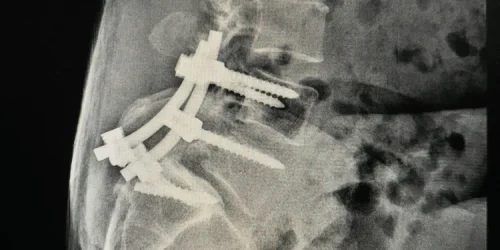

We’re covering the more commonly encountered adult degenerative scoliosis. This is a condition where the spine starts to twist on itself, particularly in the lower back — called the lumbar spine. And what happens is, as the bones twist and settle from degenerative disc disease, you get a rotation of the spine — usually two curves. And this is the condition we’re talking about, where patients will go see their doctor — usually a surgeon — with back pain, and the surgeon will tell them they have to have a fusion that involves virtually their whole spine.

We’re seeing more and more X-rays and patients out there having these types of highly invasive, extensive spinal fusions — and oftentimes it’s multiple fusions occurring over the course of a few years. So why are surgeons recommending so much spinal fusion for scoliosis? Unfortunately, the answer is that they just don’t know how to identify the actual pain source that the patient is presenting for.

You don’t need a major fusion done for scoliosis to treat back pain. That is absolutely unnecessary. In all my years of experience, there are only a few cases of patients every year in the United States that actually really need their scoliosis corrected to get rid of their pain or other symptoms such as deformity or difficulty walking. But the vast majority of people having fusion done these days for scoliosis are having it done because they believe the scoliosis is causing their back pain — and that is not the case.